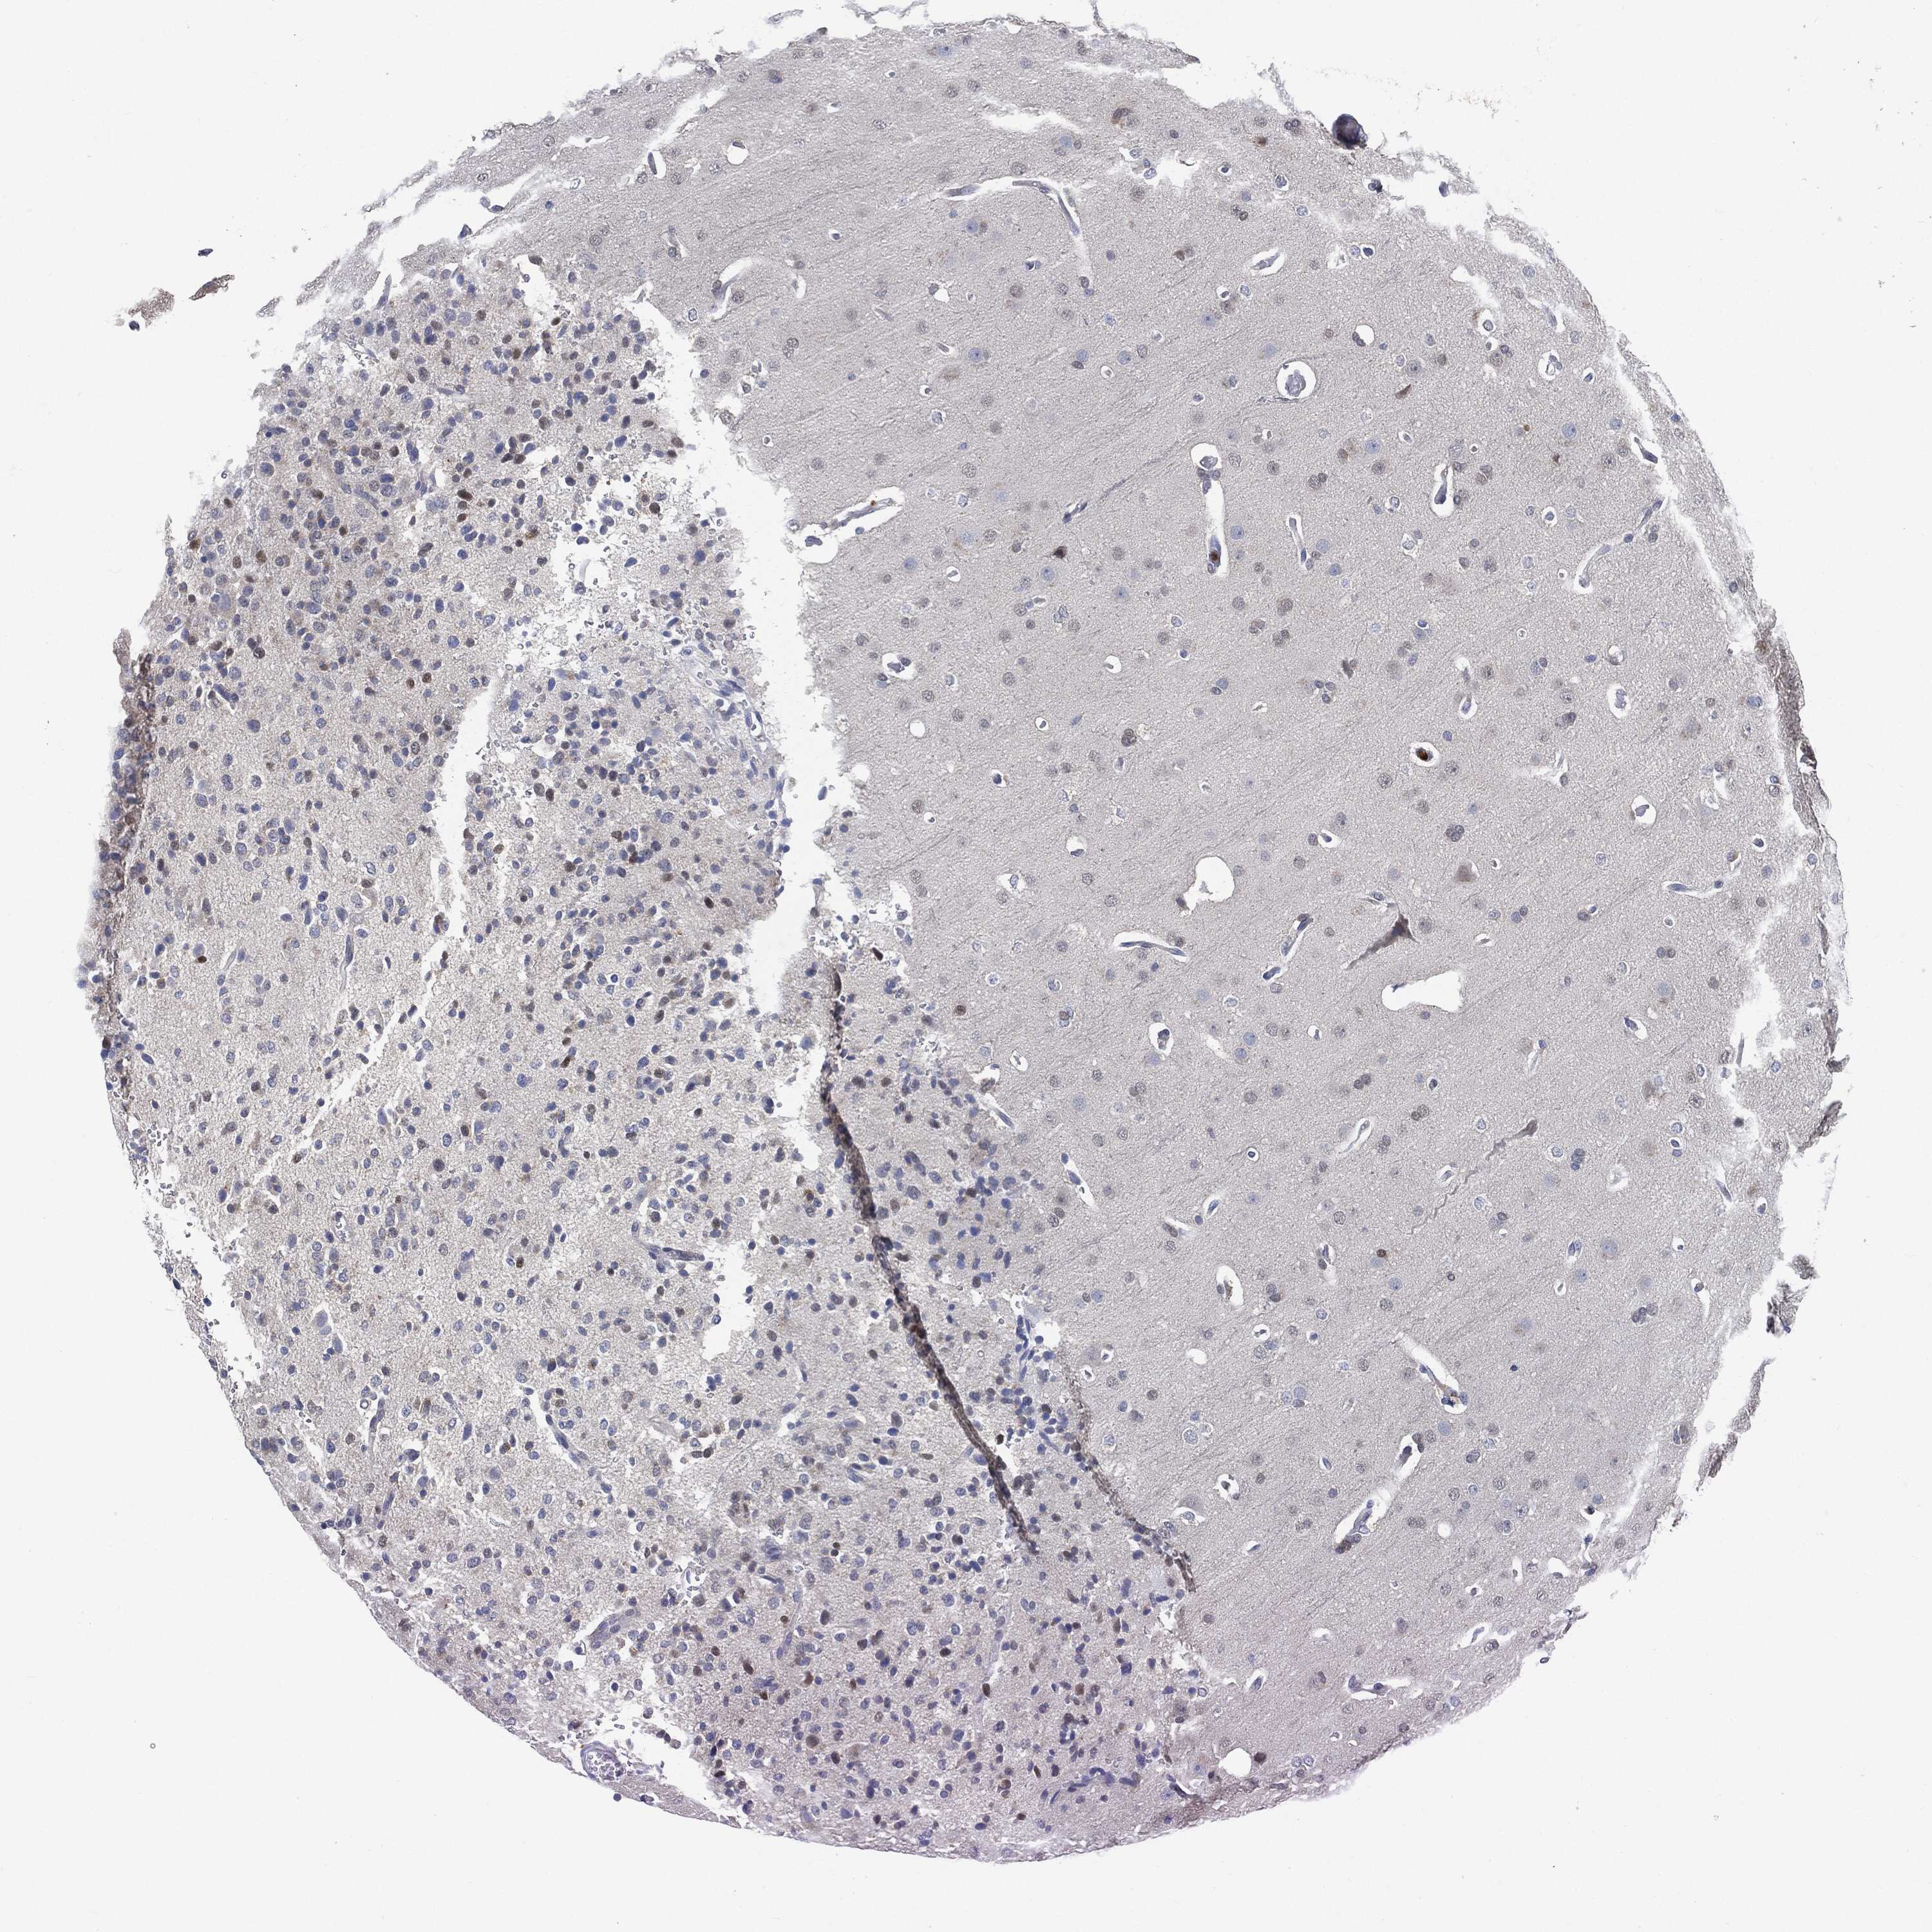

GLIOMA - Protein expressioni

A mouse-over function shows sample information and annotation data. Click on an image to view it in a full screen mode. Samples can be filtered based on level of antibody staining by selecting one or several of the following categories: high, medium, low and not detected. The assay and annotation is described here.

Note that samples used for immunohistochemistry by the Human Protein Atlas do not correspond to samples in the TCGA dataset.

Antibody stainingi

Antibody staining in the annotated cell types in the current human tissue is reported as not detected, low, medium, or high, based on conventional immunohistochemistry profiling in selected tissues. This score is based on the combination of the staining intensity and fraction of stained cells.

Each image is clickable and will lead to virtual microscopy that enables deeper exploration of all samples and also displays staining intensity scores, fraction scores and subcellular localization as well as patient and tissue information for each sample.

Antibody HPA003903

Antibody HPA072756

Antibody CAB026000

Staining

High

Medium

Low

Not detected

Intensity

Strong

Moderate

Weak

Negative

Quantity

>75%

75%-25%

<25%

None

Location

Nuclear

Cytoplasmic/membranous

Cytoplasmic/membranous,nuclear

Glioma, malignant, High grade

Glioma, malignant, NOS

Glioma, malignant, Low grade